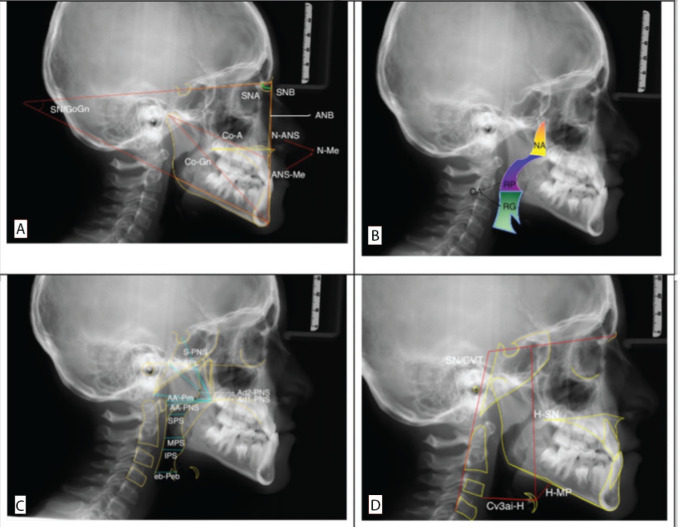

Methods: This retrospective study analyzed pre-treatment cephalograms of a total of 180 patients with Class I (45 girls, 45 boys) and Class III (maxilla or maxillo-mandibular origin) (45 girls, 45 boys) malocclusions. Linear and angular measurements were conducted on lateral cephalograms utilizing the GNU Image Manipulation Program (GIMP 2.10.18, NY, USA; https://www.gimp.org/). The pharyngeal airway areas were computed utilizing AUTOCAD (Autodesk 2018, San Rafael, CA, USA). The Independent Samples t-test and Mann-Whitney U test were employed for comparative analysis of variables across groups. The forward selection method was employed in conjunction with regression analysis.

Results: No significant differences were observed in the nasopharyngeal area (NA; mm2) across the malocclusion groups and genders. In Class III girls, the oropharyngeal area (OA; mm2), retroglossal (RG; mm2) area, and superior pharyngeal space (SPS; mm) were significantly larger than those of Class III boys, and Class I girls (p<0.05). The inferior pharyngeal space (IPS; mm) was significantly larger in Class III girls compared to Class III boys (p<0.05). Girls with Class I/III malocclusions demonstrated a more pronounced head posture than boys (p<0.05).